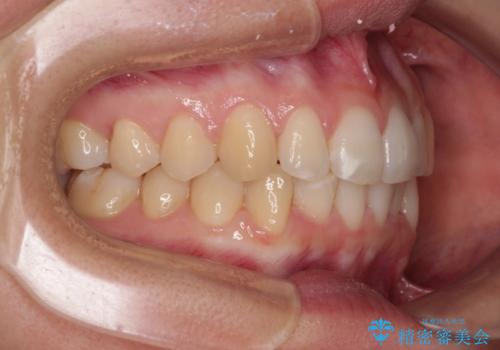

【モニター】前歯のデコボコとクロスバイト インビザラインによる矯正治療

- 上下のクロスバイトと前歯のデコボコを気にして来院された患者様です。

インビザラインを用い、IPR(歯と歯の間を削る)と歯列全体を拡大させることで、歯並びを整えていくこととしました。

下の歯が隠れてしまうほどでしたが、深い咬み合わせも改善され、顎への負担も軽減されました。